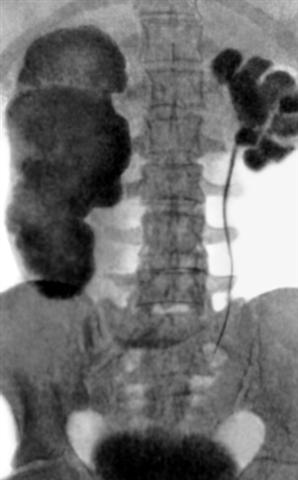

Рис. 2. Урограмма при двустороннем гидронефрозе: с обеих сторон видны четко контрастированные полости на месте резко расширенных почечных чашечек и лоханок.